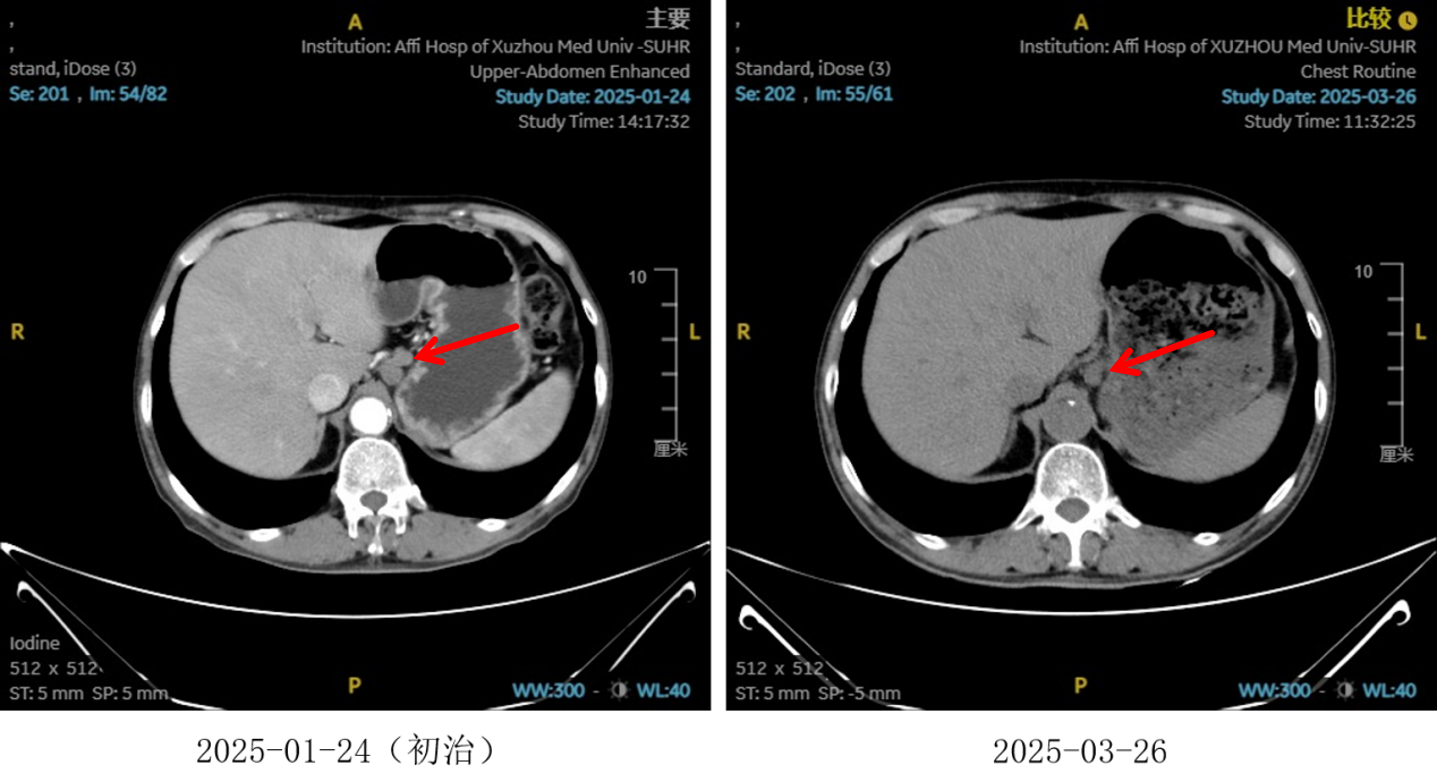

图2:2周期化疗联合抗血管治疗后食管癌病灶对比

图3:2 周期化疗联合抗血管治疗后淋巴结对比

图4:2周期治疗后影像学 [图左:“食管Ca化疗后”,食管胸中下段管壁增厚,较厚处管壁约15mm,边缘模糊,病灶局部与邻近大血管、气管壁分界不清。图右:纵隔内(3P、4、7)、左肺门及胃小弯旁示多发稍大、增大淋巴结影,部分融合,较大者大小约16mmx13mm。]

疗效评估

治疗2周期后,食管壁厚度由17mm降至15mm,淋巴结由18mm×15mm缩小至16mm×13mm;4周期后,食管壁进一步缩至12mm,淋巴结明显减少;6周期后,食管壁仅余10mm,纵隔内仅见小淋巴结影,疗效评估“接近CR”。